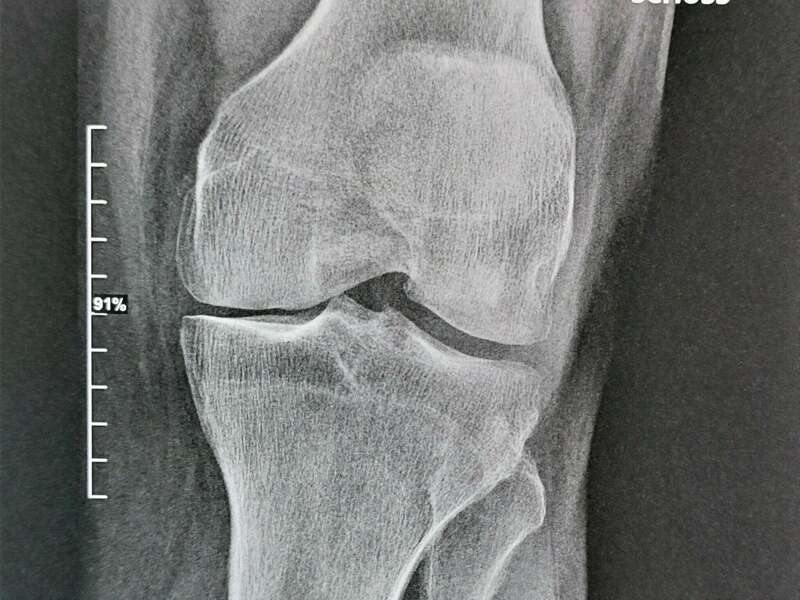

Comment faire le diagnostic d'arthrose?

Le diagnostic d’arthrose repose sur l’interrogatoire et l’examen clinique. Le médecin interrogera le patient pour déterminer la nature des symptômes et leur évolution, recherchera d’éventuels facteurs de risque, et étudiera le retentissement sur la vie quotidienne.

L’examen clinique évaluera la mobilité articulaire et recherchera un diagnostic différentiel : douleurs projetées sur le genou d’une pathologie rachidienne ou de la hanche, tendinite, lésions ménisco-ligamentaire.

Elle sera confirmée par des examens radiologiques tels que des radiographies du genou. En cas de doute diagnostic ou afin de rechercher d’éventuelles lésions associées, un scanner et/ou une IRM pourront être prescrits.